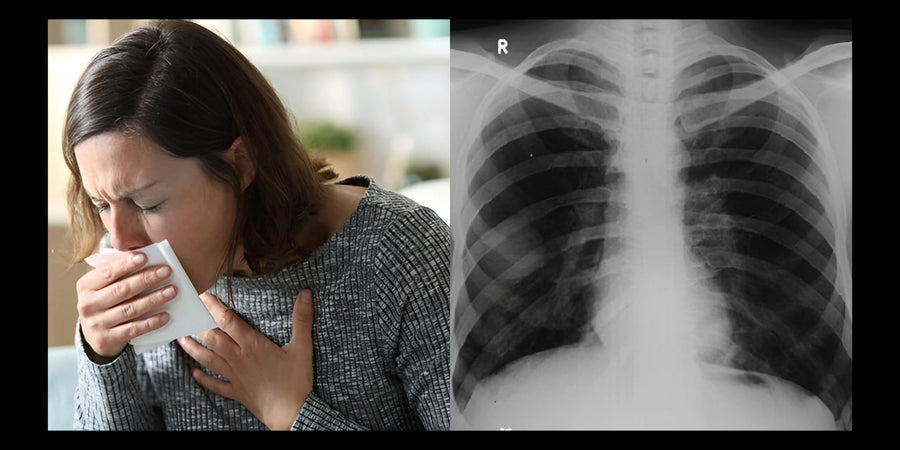

How I went from shortness of breath and coughing to breathing easily

Are you often short of breath, have a cough or feel that your lungs are not functioning optimally? Even though your doctor...